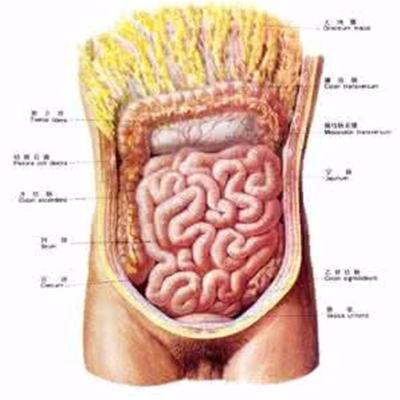

Gastric cancer, liver cancer and lung cancer are not only common diseases with high mortality, but also one of the most common malignant tumors in human body. This terrible disease deprives many people of their precious lives year by year. For patients, early treatment is needed. Why can advanced lung cancer coma, now let's understand.

First: when lung cancer is advanced, it is easier to produce coma symptoms. If the patient is comatose, then the cachexia is often studied seriously, and even the patients with this disease have the trend of lung cancer brain metastasis. There are cancer cells in the brain, so coma is more likely to occur at this time.

Second: advanced lung cancer patients need to do some head CT examination to see if there is brain metastasis. And you can go to a big hospital for MRI diagnosis. Of course, once a patient has cancer, he can't eat hair or goose.

Third: once the patients with advanced lung cancer have the symptoms of coma, they can't take medicine casually. At this time, we need to use drugs to reduce brain edema under the guidance of doctors. Then you can use mannitol to reduce blood pressure.

The patient needs to do some further head CT examination to see if there is brain metastasis. And you can go to a big hospital for MRI diagnosis. Of course, once a patient has cancer, he can't eat hair or goose.